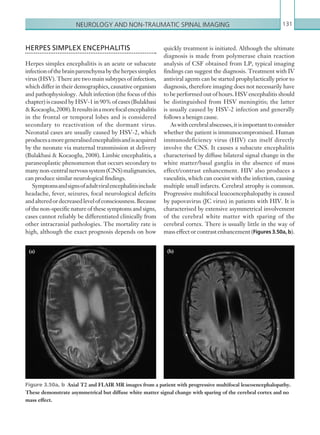

• 164.

Chapter 4142 The ultrasoundappearance has also been likened to a ‘pseudokidney’, with the combination of hypoechogenic bowel wall and hyperechogenic mesenteric fat (Figure 4.2). In patients where no evidence of intussusception is seen, other pathology that may mimic the presenting features should be considered (e.g. appendicitis). Fluoroscopic air enema The aim of an air enema is to identify the site of the abnormality and to force the intussusceptum into its normal position. This appears as a round, intraluminal massthatmovesretrogradewithincreasingairpressure. Successful reduction is demonstrated by reflux of gas into the small bowel and the resolution of the soft tissue mass (Figures 4.3a, b). Insufflation air pressures of up to 120 mmHg should be used up to a maximum of three attempts. If repeated insufflation of the bowel with air is unsuccessful, surgical intervention should be considered. Success rates of over 80% have been suggested following air reduction. However, 5–10% of intussusceptions may reoccur, usually within the first 72 hours, therefore close attention to worsening Figure 4.2  Ultrasonogram of the bowel in the longitudinal plane. ‘Pseudokidney’ appearance is shown as the hypoechoic bowel wall with central echogenicity due to the mesenteric fat herniating into the distal bowel lumen. Figures 4.3a, b  AP images of the abdomen during fluoroscopic air enema reduction. (4.3a) The intussusceptum can be seen at the hepatic flexure outlined by gas instilled within the colon (arrow). (4.3b) The intussusception is no longer visible within the colon, with reflux of gas into the small bowl indicating reduction of the intussusception. abdominal symptoms should be made (Donnelly et al., 2005). Contraindications to air enema reduction include bowel perforation, haemodynamic instability or signs of peritonism/bowel ischaemia. (a) (b) K22247_C004.indd 142 16/05/15 3:10 AM

• 165.

Paediatric imaging 143 BOWELMALROTATION Bowel malrotation is considered a surgical emergency owing to the high risk of bowel ischaemia. The vast majority of patients present in the first few months of life (many in the first week of life); however, the condition may be first diagnosed in older children and even in adults, often with a history of chronic symptomatology. Presenting features include bilious vomiting, abdominal distension, weight loss and irritability. Innormalindividuals,duringdevelopment,thesmall bowel rotates about the mesentery in an anticlockwise direction of 270 degrees. The duodenojejunal (DJ) junction is positioned in the left upper quadrant and the caecum in the right lower quadrant, with a long mesenteric base, which secures the bowel leaving it unlikely to twist. Malrotation is an embryological abnormality whereby the rotation and position of the bowel is altered and results in an abnormal mesenteric attachment, which is often short with an increased likelihood of midgut volvulus. As a result of this developmentalabnormality,thenormalpositionsofthe DJ junction and caecum are altered and it is this feature that is utilised in diagnostic imaging. Radiological investigations An upper GI contrast study should be performed to assess the position of the DJ flexure. A dense contrast medium should be used (e.g. barium) with the patient positioned in both supine and lateral positions. A small bowelfollowthrough/contrastenemacanbeperformed to demonstrate the position of the caecum in equivocal cases. (See Table 4.2.) Plain films An AXR is rarely normal. Classically, there is a paucity ofgasintherightlowerquadrantwithnon-visualisation of the caecum. A meniscus of soft tissue outlined by gas within the colon may also be demonstrated. Depending on the site of the intussusception, small bowel obstruction may be apparent. A normal variant of the position of the sigmoid colon in the right lower quadrant, and the associated presence of gas in this position, may provide false reassurance for those presenting with ileocolic intussusceptions, a potential pitfall. Computed tomography CT is not advised in patients presenting acutely; however, an intussusception may be seen incidentally in patients presenting with non-specific symptoms, particularly adult patients. The appearances on CT are similar to those seen on ultrasound, with telescoping of bowel with alternating layers of bowel and mesenteric fat. The bowel must be assessed in detail, in particular looking for an underlying lesion that may be acting as a lead point. Bowel obstruction may also be seen. Key points • Intussusception is a life-threatening condition due to the risk of bowel ischaemia and perforation, and so prompt diagnosis is necessary. • Multiple forms of imaging are usually used to confirm the presence of intussusception, with an air enema reserved for both diagnosis and treatment. • If an air enema fails to reduce an intussusception after three attempts, the patient should be considered for surgical treatment. Report checklist • Recommend urgent air enema reduction in cases of intussusception – the patient will often require prior fluid resuscitation and stabilisation. Reference Donnelly LF, Jones BV, O’Hara SM et al. (2005) (eds) Diagnostic Imaging: Pediatrics, 1st edn. Friesens, Altona, pp. 74–77. MODALITY PROTOCOL ­Fluoroscopic upper ­gastrointestinal contrast study Standard formulation barium (e.g. Baritop) should be instilled into the stomach either orally or via a nasogastric tube. Contrast should be followed and observed to pass into the duodenum and to the DJ flexure, and the position should be documented. Table 4.2  Bowel malrotation. Imaging ­protocol. K22247_C004.indd 143 16/05/15 3:10 AM

• 166.